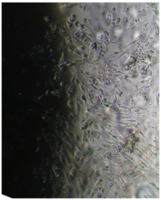

Образцы исследуемого материала (фрагменты имплантата неправильной формы из титанового сплава в виде пластинок размерами 2,8х2,8 мм, толщиной 2 мм и массой ~ 65 мг) помещали на дно культуральных чашек, после чего высевали фибробласты в стандартной концентрации.

Под влиянием изучаемого металла прикрепление клеток к дну культуральной чашки несколько ухудшается, в результате чего плотность монослоя через сутки наблюдения значительно меньше, чем в контроле (табл. 18).

В то же время клетки прикрепляются равномерно по всей площади дна чашки, не проявляя какого-либо сродства к образцу.

В течение всего срока наблюдения фибробласты сохраняют характерную морфологию, скорость и характер роста (рис. 41).